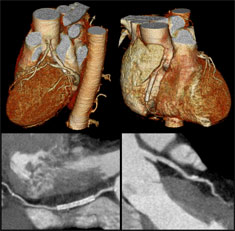

This scan, provided by Toshiba, shows a stent in a coronary artery in a view of the exterior of the heart (top) and also in cross-section through the coronary artery in which it was inserted (bottom).